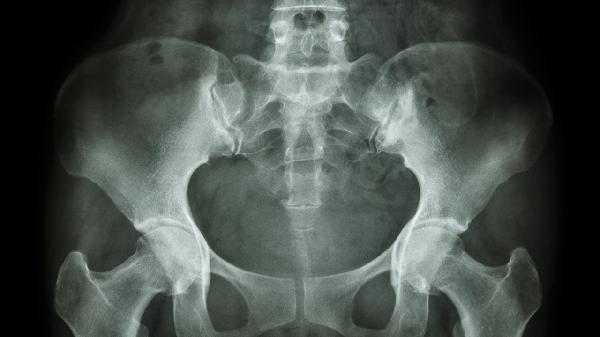

当囊肿直径超过5厘米或合并感染时,可能表现为局部红肿热痛、皮肤破溃流脓,甚至引发全身发热。长期存在的囊肿可能压迫坐骨神经,出现下肢放射性疼痛或麻木感。极少数情况下囊肿可能发生恶变,表现为短期内迅速增大、质地变硬或与周围组织粘连。上述情况需通过超声或磁共振检查明确性质,必要时行穿刺抽液或手术切除。